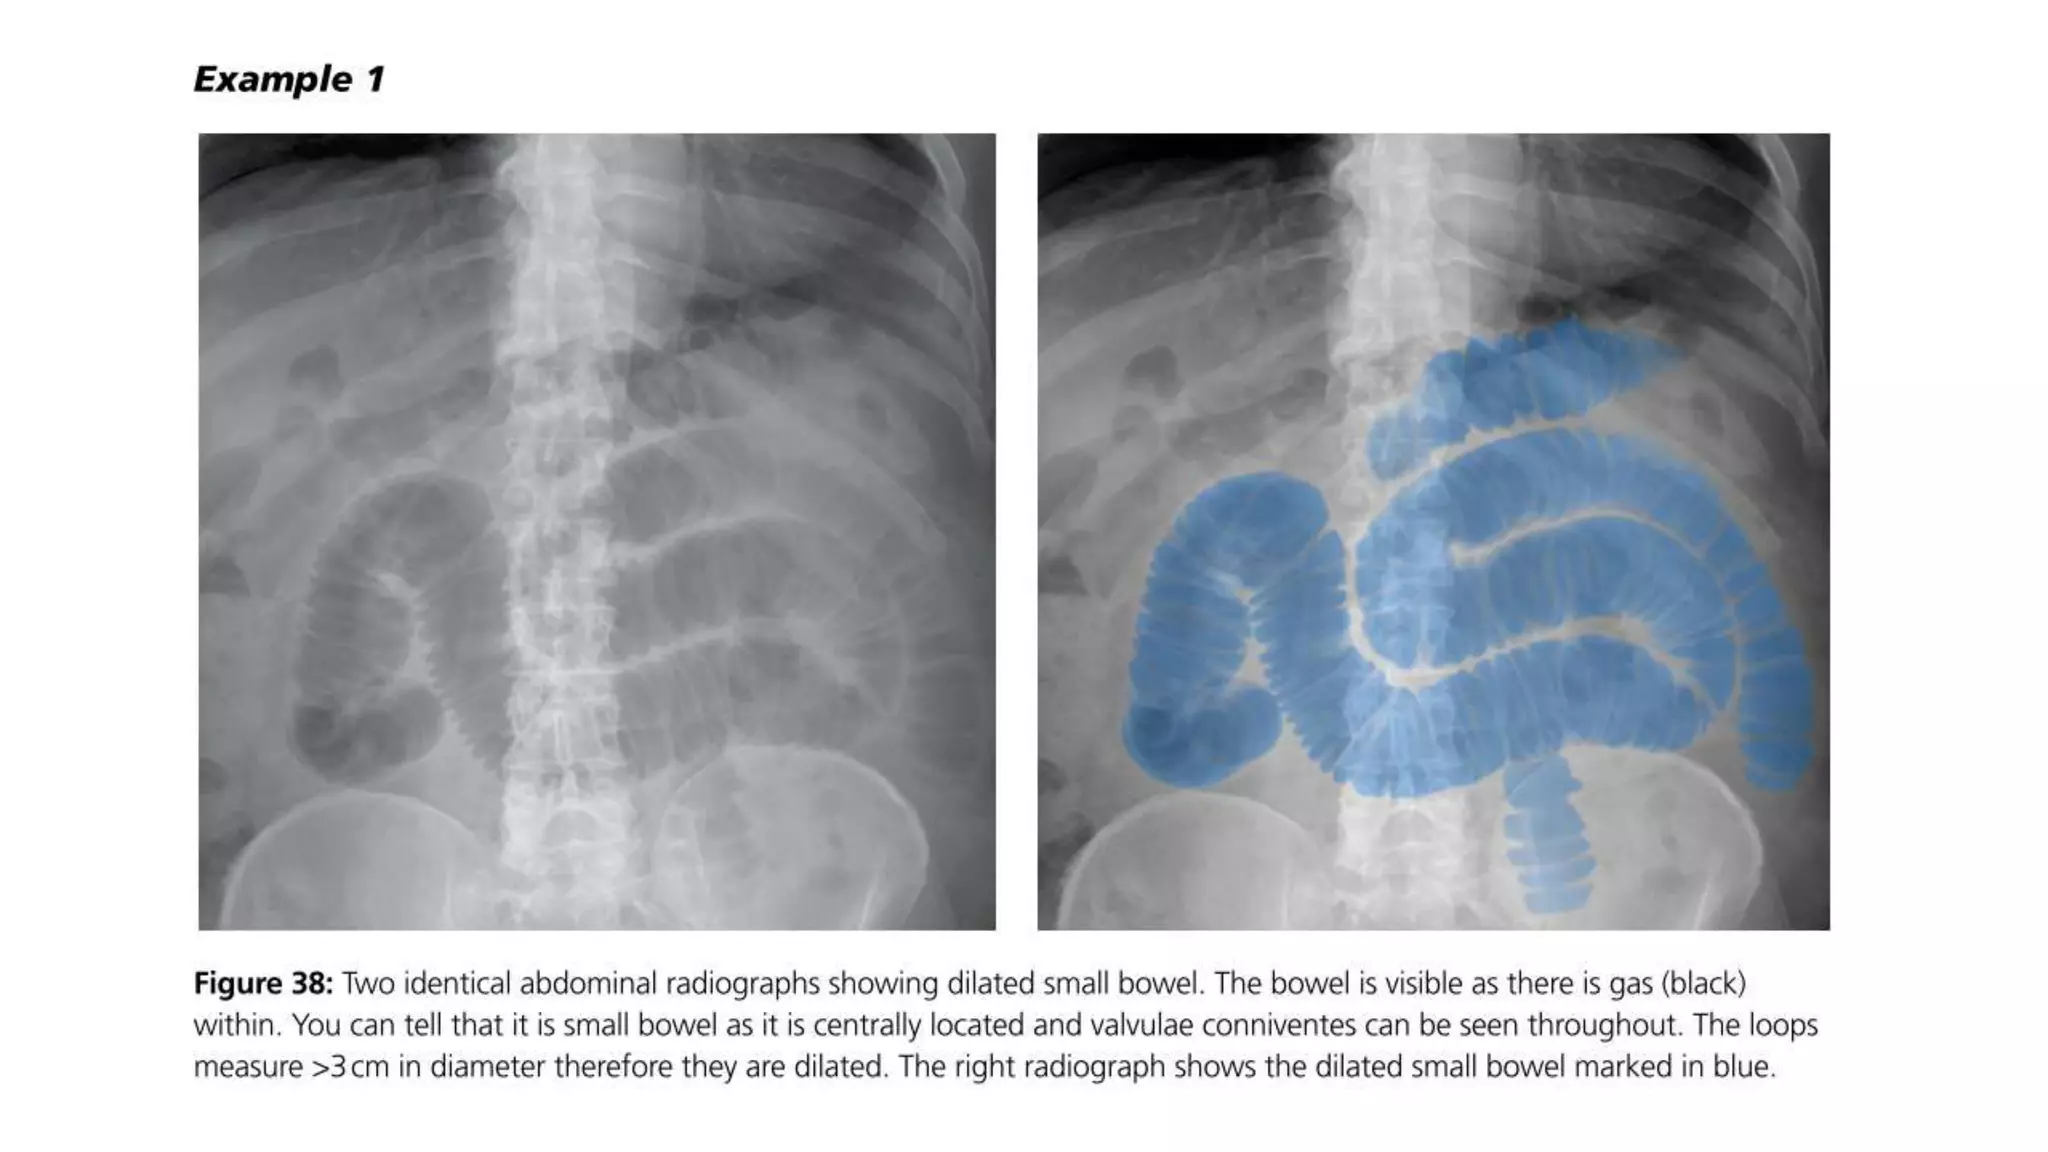

• Dilation >3 cm: The small bowel is dilated if it measures over 3 cm in

diameter.

• Central location: The dilated loops are more likely to be centrally

located on the abdominal radiograph.

• Valvulae conniventes: These are the mucosal folds of the small

intestine. They are thin, closely spaced and classically seen as a

continuous thin line across the entire width of the bowel.

• Air fluid level in upright position

• #41 Note: The height of an adult vertebral body is approximately 4 cm. You can use this as a quick comparison to estimate the diameter of the bowel. Note: Large bowel tends to be peripherally located.